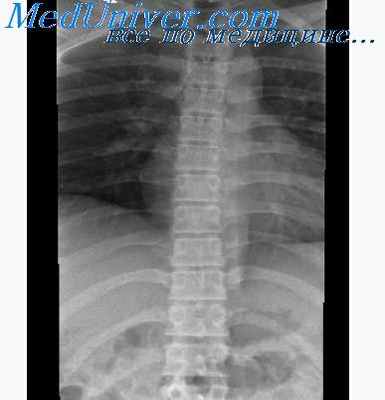

При патологии позвоночного столба и спинного мозга, а также его корешков производят рентгенографию нижнегрудного и пояснично-крестцового отделов позвоночного столба в двух проекциях (прямой и профильной) с предварительной подготовкой кишок. При рентгенографии других отделов его эту подготовку не проводят. Спондилография позволяет определить состояние тел позвонков, дужек, отростков, его возрастные особенности, ширину позвоночного канала, физиологических искривлений, состояние межпозвонковых пространств, врожденные дефекты (незаращение дужек, сакрализация, люмбализация, другие аномалии).

Иногда необходимо дополнить обзорные спондилограммы косыми проекциями или снимками с функциональной нагрузкой для выявления ограничения подвижности, препятствий. Одни снимки производят в положении больного лежа, другие — в положении сидя (например, шейных позвонков). При подозрении на перелом шейного отдела позвоночного столба рентгенограмму производят только в положении больного лежа на спине с оттянутыми плечевыми суставами книзу по оси, при подозрении на перелом других отделов его — только в положении на животе с боковым расположением кассеты для профильной проекции во избежание дополнительной травмы спинного мозга отломками позвонка.

Для более достоверного суждения об изменениях структуры позвонков или выявления деталей патологического процесса обычные обзорные спондилограммы дополняются томографией позвоночного столба.

Рентгенографические снимки сначала выполняют без введения контрастного вещества в 2-х взаимно перпендикулярных проекциях. После введения контрастирующего вещества выполняют серию рентгенологических снимков через определенные промежутки времени в 2-х а иногда и в 3-х проекциях (правая латеральная, вентро-дорсальная, косая проекция) для лучшей визуализации и латерализации поражения.